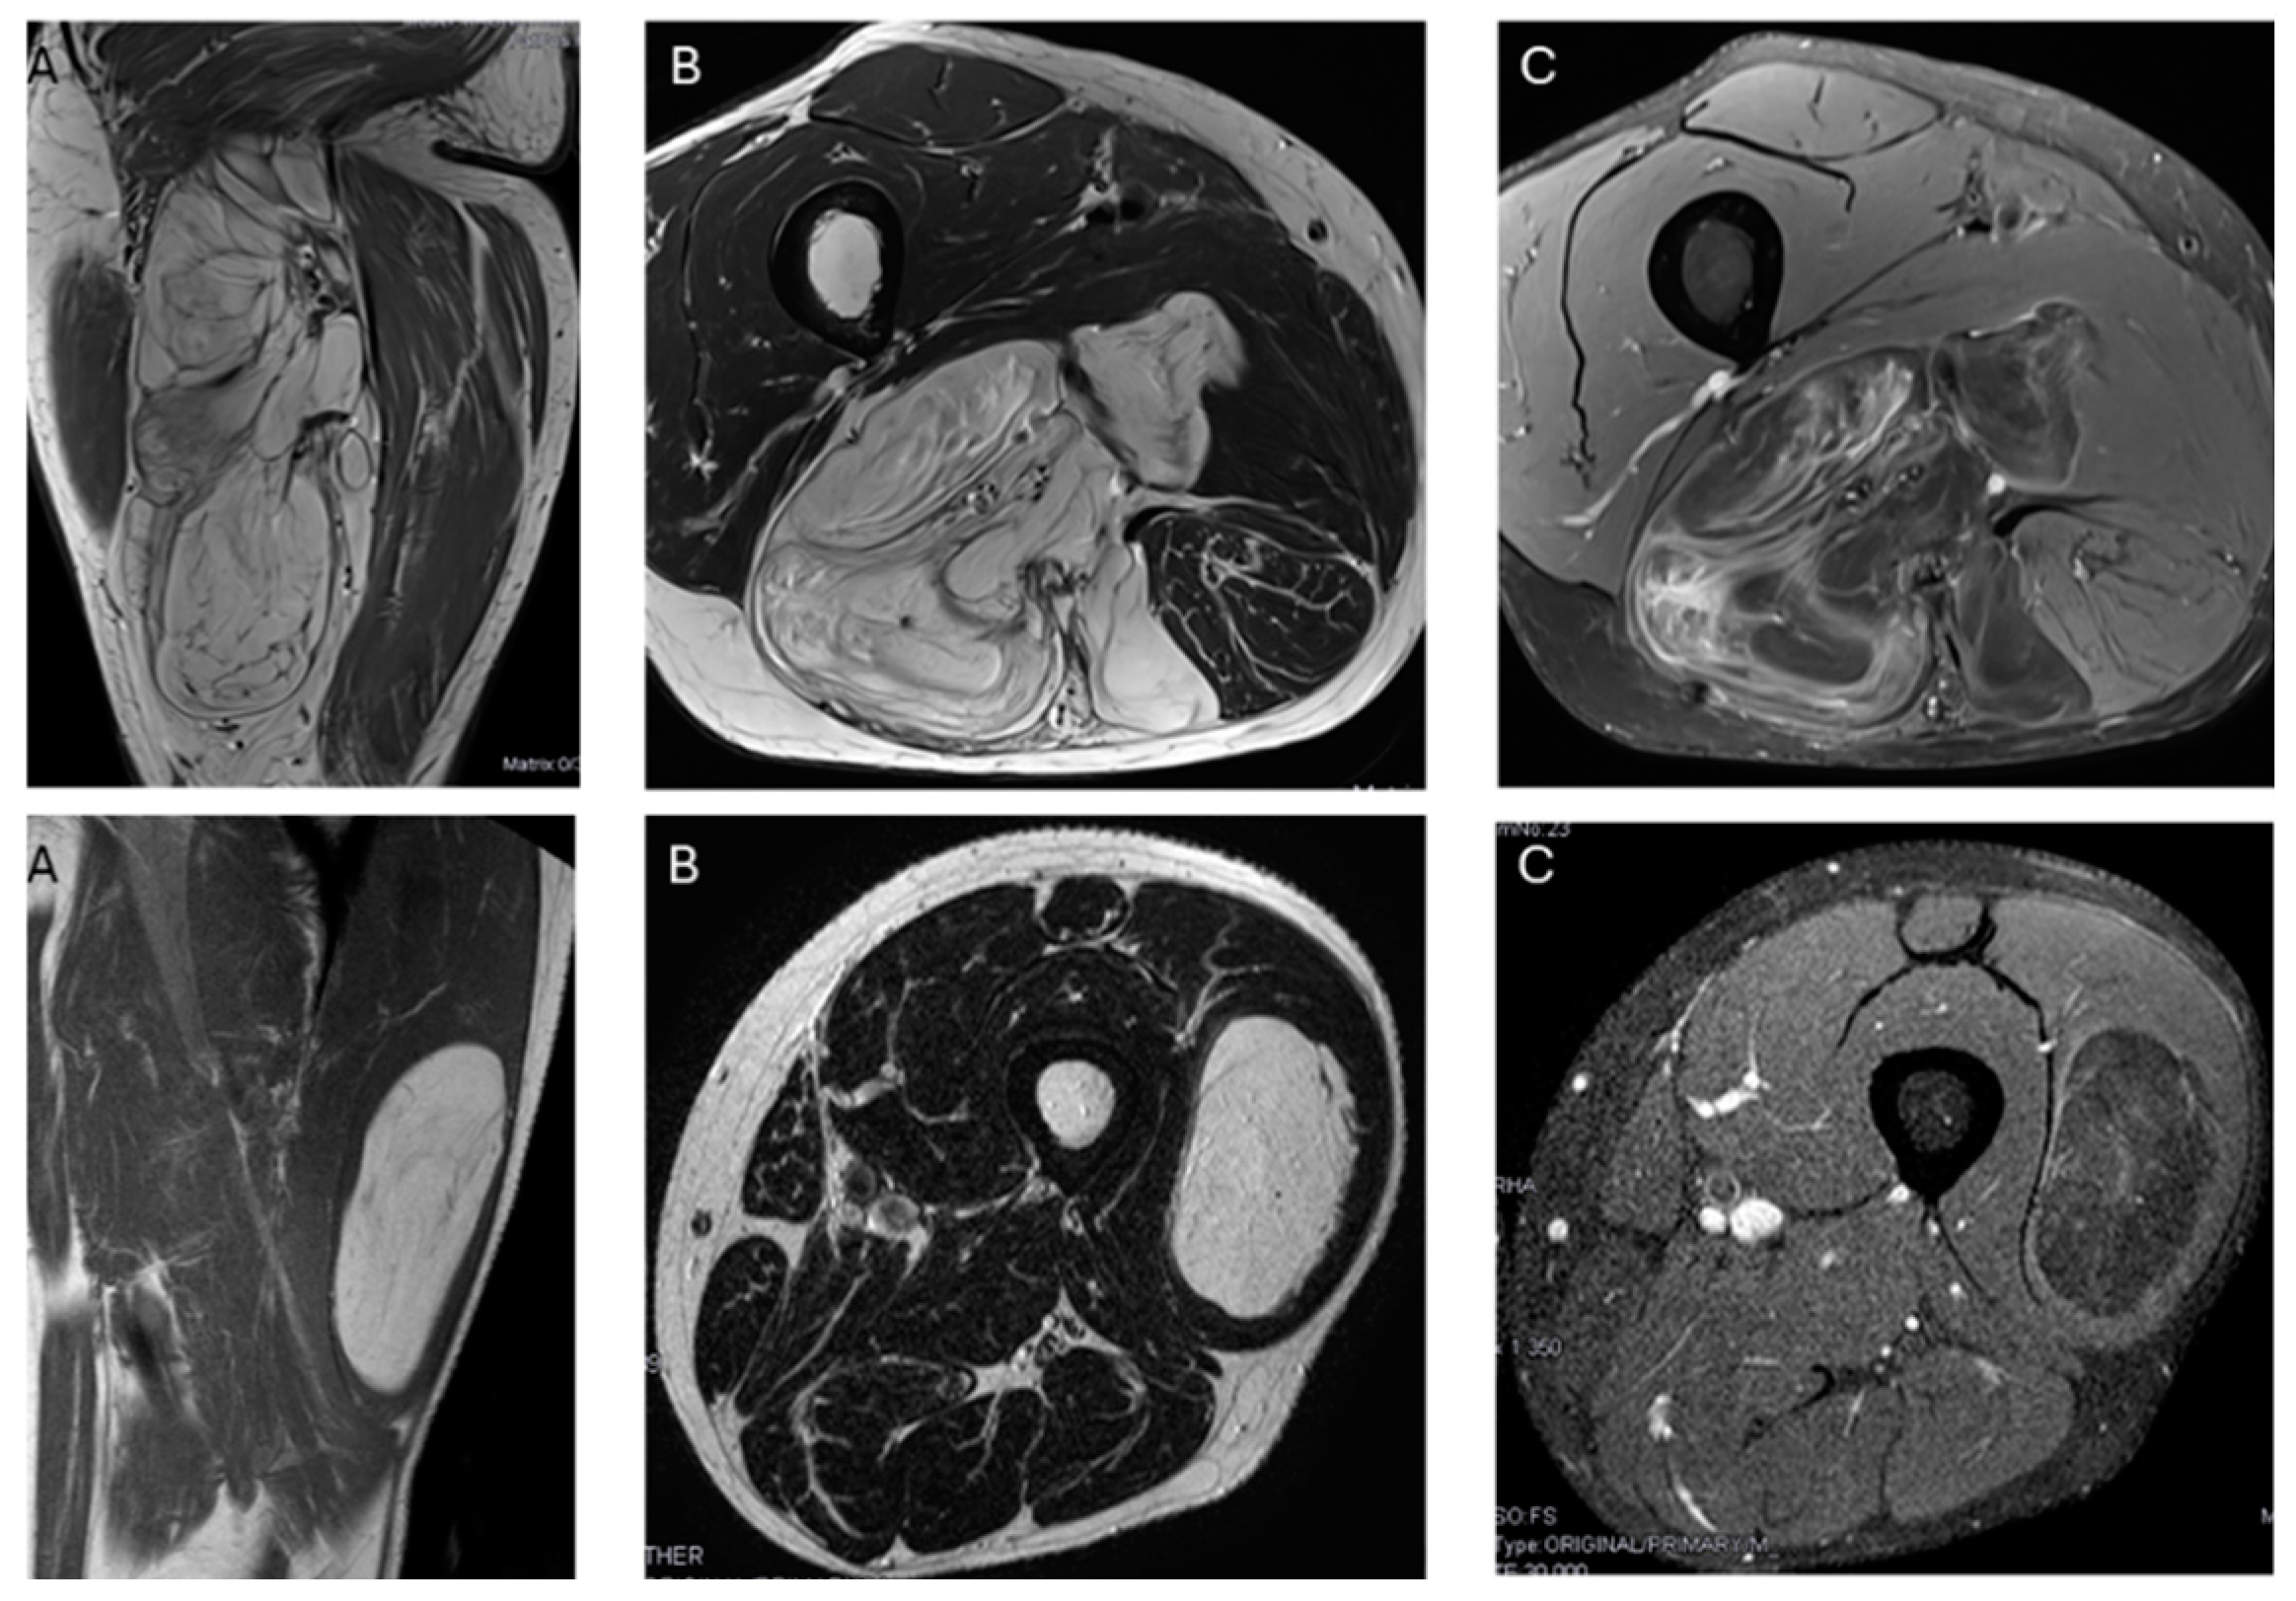

The presence of non-fat nodules was not significant, as there were no differences between lipomas and ALT (p value = 0.096). Twenty lipomas and ALTs presented non-fat nodules, of which one out of twelve lipomas and six out of eight ALTs showed more than one non-fat nodule (p value < 0.001). However, there were no significant differences in the size of the largest non-fat nodule between lipomas and ALTs (p value = 0.550).

Regarding the presence and size of non-fat nodules, there was no difference between lipomas and ALTs; however, in our series, there was a difference in the number of nodules.

There was typically more than one non-fat nodule in ALT, while lipomas usually had only one (Figure 6). Unlike other studies, which suggested that non-fat nodules larger than 1 cm in diameter are an important discriminator favoring ALT over lipoma [17], our findings did not support this distinction.

We do not know the exact explanation for these results, but ALTs are generally larger than lipomas, which may explain why they tend to have more than one non-fat nodule, although these nodules are not significantly larger in ALTs than in lipomas.

There are some limitations in this study. First, septa and non-fat nodular area enhancement were not investigated. Although Nardo’s multicenter study concludes that qualitative MR variables help in characterizing lipomas and ALTs, contrast enhancement does not, and may even cause confusion [14]. Additionally, contrast-enhanced MRI sequences increase both the time and cost of the procedure. Another limitation is the size imbalance between the lipoma and ALT samples, which reflects what happens in clinical practice. The differences in sample size may affect the results, aside from the bias introduced by the subjective visual analysis of MRI images by radiologists who tend to overdiagnosis ALT. Our approach to managing deep fatty soft tissue tumors based on their MRI characteristics, (Figure 6) would reduce the number of biopsies required for these two tumor types, minimize uncertainty for expert radiologists, and provide significant support to less experienced or generalist radiologists without specific training in soft tissue tumors.

Figure 6. Nodules. Sagittal T1W images show a deep lipomatous mass in the popliteal fossa, measuring 27 cm along its long axis and with two non-fat nodules (arrows) Diagnosis: ALT (MDM2 positive). Axial T2W images present a lipomatous tumor in quadriceps, with two non-fat nodules (asterisks) Diagnosis: ALT (MDM2 positive).